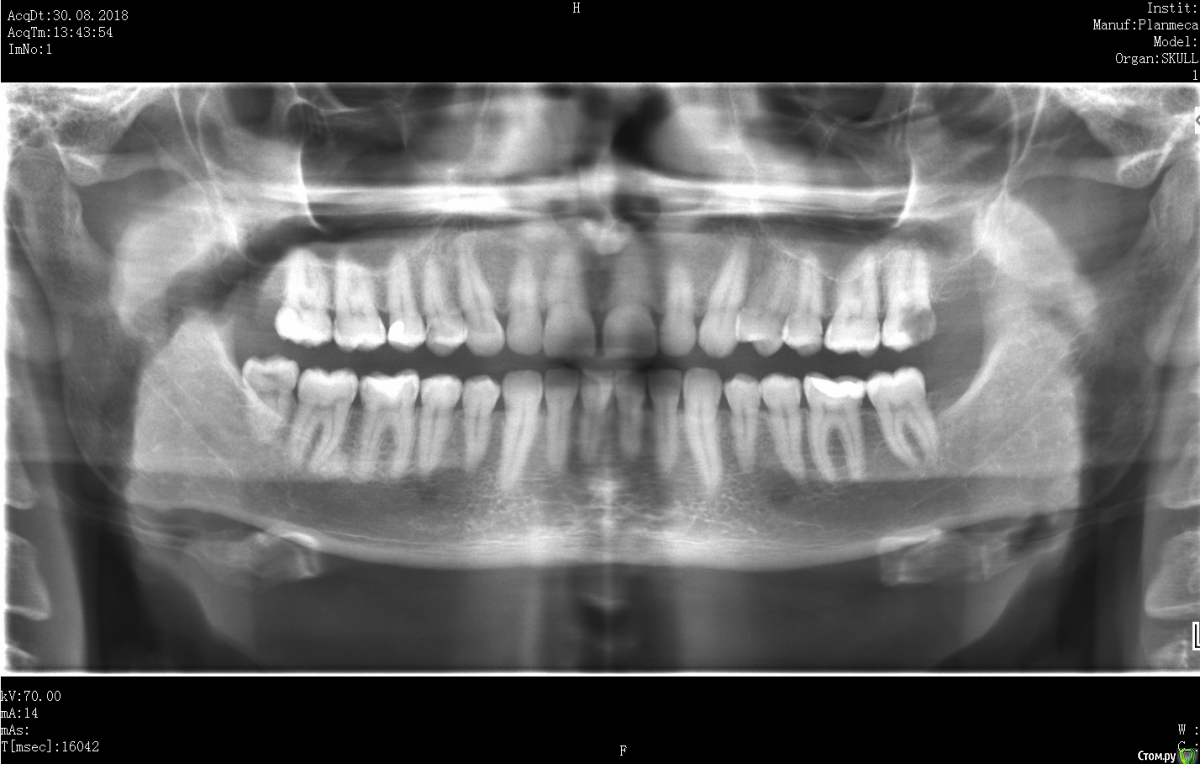

Xealer Опубликовано 20 апреля, 2017 Поделиться Опубликовано 20 апреля, 2017 (изменено) Здравствуйте! Меня зовут Руслан, мне 31 год.Меня 2 месяца назад стал беспокоить зуб 27.Моя цель: вылечить зуб 27 с минимальным вмешательством, сохранить нервы в пульпе. После этого вылечить зуб 17.Предыстория в спойлере:удалено администраторомТеперь зуб частично разрушен, видимо пломба отвалилась. Диагноз - пульпит.До этого боль была ноющая, сильно не беспокоила.Вчера полчаса болел сильно, сейчас снова утихла.Вопрос 1: Означает ли это, что пломба была установлена плохо?Стал ходить по разным стоматологам, с хорошей репутацией(подробности в спойлере) удалено администраторомудалено администраторомбыл только на консультациях: удалено администратором Сказал, что нужно сделать 3d томографию всех зубов и ставить коронку на 27. Цена 10 тыс руб. удалено администратором(стаж более 25 лет, высокая репутация в интернете): Посмотрел 3d томографию, сказал, что лучше поставить коронку, но можно поставить пломбу! Когда, я спросил про материалы для коронки, сказал, что можно поставить: - металлокерамическую коронку (CoCr) - титан Стал немного путаться в цене. Отправил к стоматологу-терапевту удалено администратором, на первоначальное лечение перед установкой коронки. Цена 12 - 15 тыс руб. Про зуб 17 сказал, что коронку ставить не надо, можно поставить пломбу.удалено администратором удалено администраторомРассказал про лечение подробнее, чем остальные, показал фотографию разрушенного зуба. Сделал 3d томографию. Назвал высокие цены, сославшись на то, что в других стоматогиях некачественные материалы, а у них качественные немецкие материалы. Цена 34-50 тыс руб включает: Сумма в руб Изготовление культевой вкладки разборной либо за 8000, либо за 15000 Изготовление металлокерамической коронки (CoCr) - Некая стандартная цена 14000 (видимо стандарная цена в моём случае не использовалась, была на бланке) - Литьевой метод 20000 - Фрезерный метод 30000 и т д Про зуб 17 сказал, что коронку ставить надо, и ставить пломбу на него неграмотно с медицинской точки зрения, так как стенка до пульпы всего 1 мм. Остальные вопросы:2. Могут ли такие цены, которые мне предложили в удалено администратором за "качественные немецкие материалы", быть честными?3. Можно ли поставить пломбу на 27, сохранив пульпу?4. Если ставить коронку на 27, то какой материал выбрать? нужен ли титан?5. Достаточно ли на 17, поставить пломбу?6. Какого стоматолога порекомендуете? Во вложении я сделал скриншот срезов 27 и 17, где расстояние до пульпы минимально. Если надо могу выложить весь файл с 3d томографией. Изменено 25 апреля, 2017 пользователем red_butler Ссылка на комментарий

Pan Опубликовано 22 апреля, 2017 Поделиться Опубликовано 22 апреля, 2017 Ваш зуб требует эндодонтического лечения, требует ли Ваш зуб ортопедического лечения( коронки) трудно оценить по представленным снимкам. Даже если учитывать утрату тканей для эндо доступа, следует оценить оставшиеся ткани для возможной реставрации зуба без применения ортопедической конструкции. 1 Ссылка на комментарий